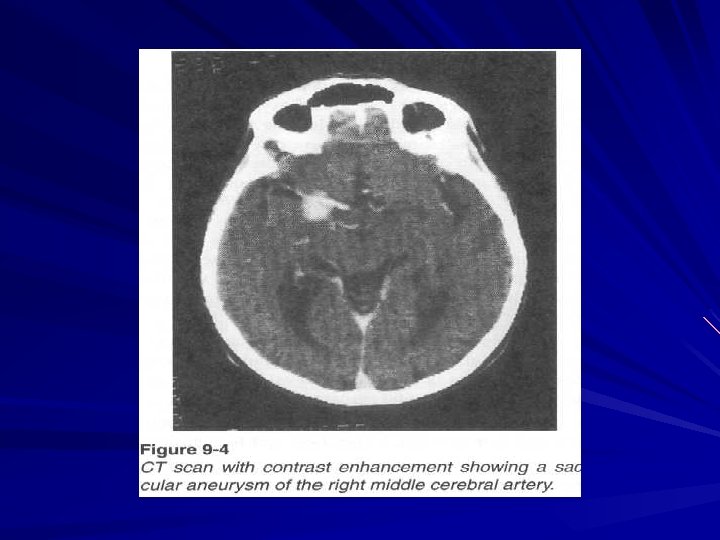

Diagnostics In blood usually leucocytosis, related lymphopenia, hyperglycemia (up to 8 – 10 mmole per liter) In liquor high pressure during lubar puncture a great number of erythrocytes are found On eye fundus – retinal hemorrhages, hypertonic angioretinopathy and Salus symptoms are observed At echoencephaloscopy there is dislocation of middle structures on 6 – 7 sm to the healthy side At angiography - aneurysm, dislocation of blood vessels, to find out zone “without vessels“ CT and MRI find out hyperdensive focuses.

Subarachnoid hemorrhage Aetiologic factors: Aneurysmatic ( 50 – 62 % ) – aneurysm rupture. Hypertensive ( at hypertension ) Atherosclerotic ( 15 % ) Traumatic ( 5 – 6 % ) Infectious – toxic ( 8. 5 % ) Blastomatose ( at tumors ) Pathohemic ( at blood diseases ) Cryptogenic ( 4 – 4. 8 % )